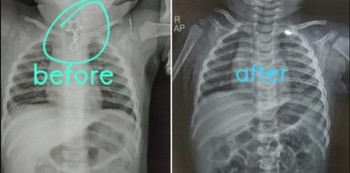

Hasil rontgen leher bayi yang menelan bandul kalung. (Linkedin/Dr Anuj Rastogi)

Tanpa pikir panjang, dokter Anuj segera melakukan rontgen dan hasilnya sungguh mencengangkan. Bandul kalung bertepian tajam itu tersangkut di area tenggorokan.

Anuj pun melakukan prosedur endoskopi kepada si bayi. Di sinilah bagian yang paling menantang menurut Anuj. Sebab, ia harus berhati-hati sekali agar tidak melukai dinding tenggorokan bayi malang tersebut.

“Ketika saya berhasil memegang bandul kalung tersebut, saya tidak bisa menggerakkannya sama sekali. Benda itu tersangkut di sana. Sedikit gerakan yang terlalu kuat saja bisa merobek dinding tenggorokan,” tulisnya.

Anuj mengaku khawatir akan gagal. Namun, berkat dukungan Dr. Gagandeep Singh Bajaj, seorang Dokter Spesialis Anestesi, yang juga kolega Anuj, operasi tersebut berhasil.

Tidak disebutkan secara terperinci, apa yang dilakukan Dr Gagandeep. Yang jelas, kata Anuj, Dr Gagandeep mengubah strategi anestesinya dan memberikan dukungan moril kepada Anuj untuk mencoba menarik bandul itu kembali.

Anuj bersyukur buat dukungan tersebut sehingga ia berhasil mengeluarkan benda berbahaya itu.